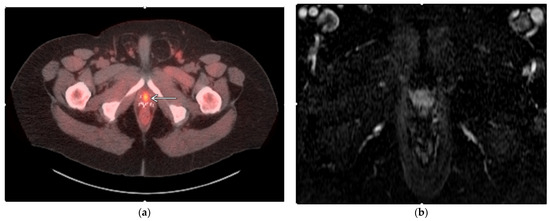

- Woodrum, D.A.; Kawashima, A.; Karnes, R.J.; Davis, B.J.; Frank, I.; Engen, D.E.; Gorny, K.R.; Felmlee, J.P.; Callstrom, M.R.; Mynderse, L.A. Magnetic resonance imaging-guided cryoablation of recurrent prostate cancer after radical prostatectomy: Initial single institution experience. Urology 2013, 82, 870–875. [Google Scholar] [CrossRef] [PubMed]

- Bomers, J.G.; Yakar, D.; Overduin, C.G.; Sedelaar, J.P.; Vergunst, H.; Barentsz, J.O.; de Lange, F.; Fütterer, J.J. MR imaging-guided focal cryoablation in patients with recurrent prostate cancer. Radiology 2013, 268, 451–460. [Google Scholar] [CrossRef]